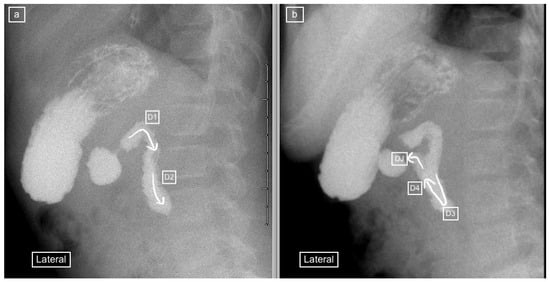

Figure 8.

Upper-gastrointestinal tract series in a 159-day-old girl with a false–negative lateral view and a diagnosis of malrotation on the frontal view. (a) Lateral view demonstrates what appears to be a normal course of the duodenum (winding arrow) into its posterior retroperitoneal position, with a presumed normal position of the duodenojejunal flexure, before the jejunum takes and anterior course. (b) Frontal view, considered the standard for this study, demonstrates the duodenal loop (from D1 through D2, D3 and D4 denoted by the winding arrow) and a caudal (low) position of the duodeno-jejunal flexure (DJ) in comparison to D1 (the positional differences denoted by the dashed lines), consistent with malrotation.